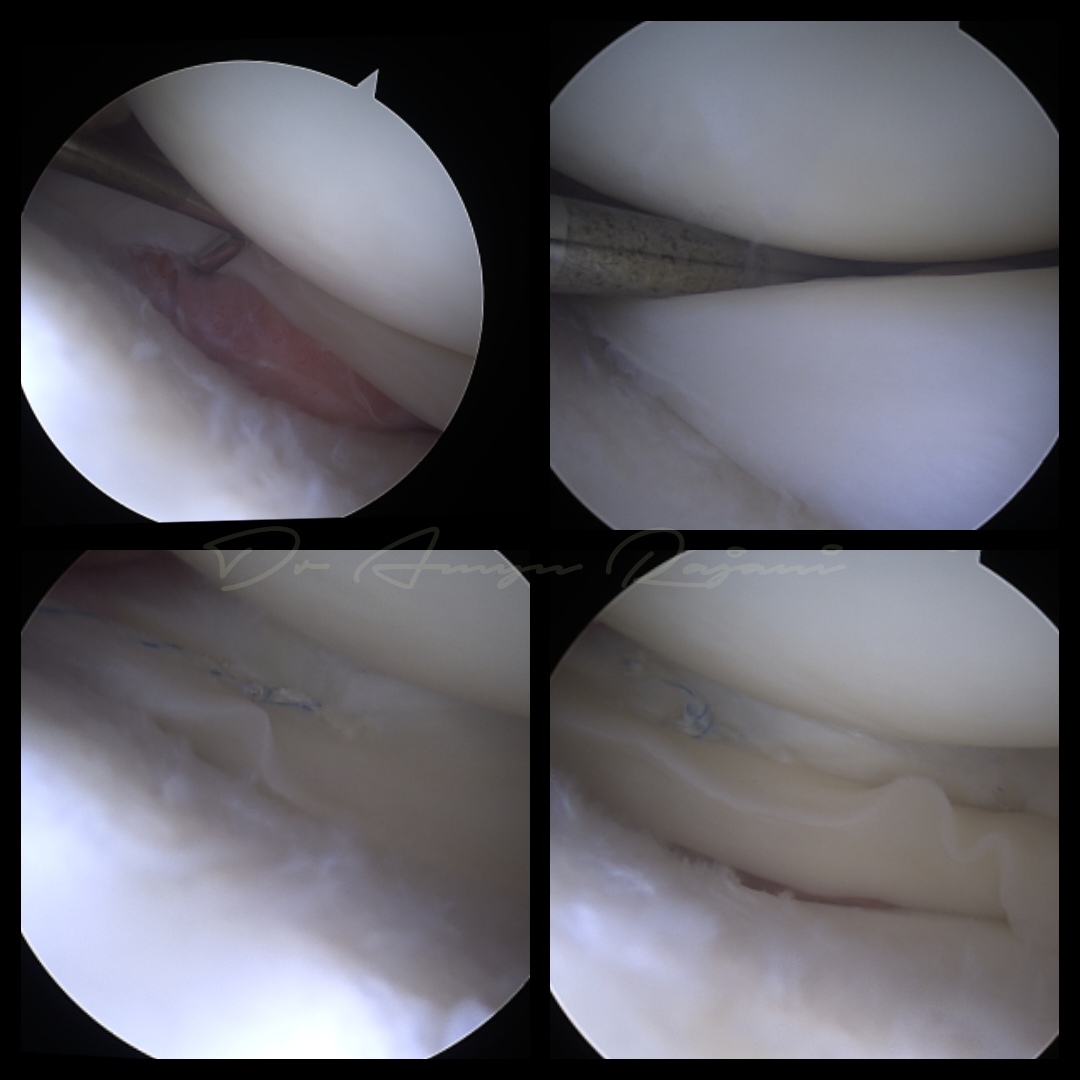

History: 25-yr-old patient was suffering from a peripheral lateral meniscus tear. Case: Take a close look at the tibial cartilage, the fraying is because of the unstable meniscus moving in and out during flexion and extension causing friction of cartilage.…